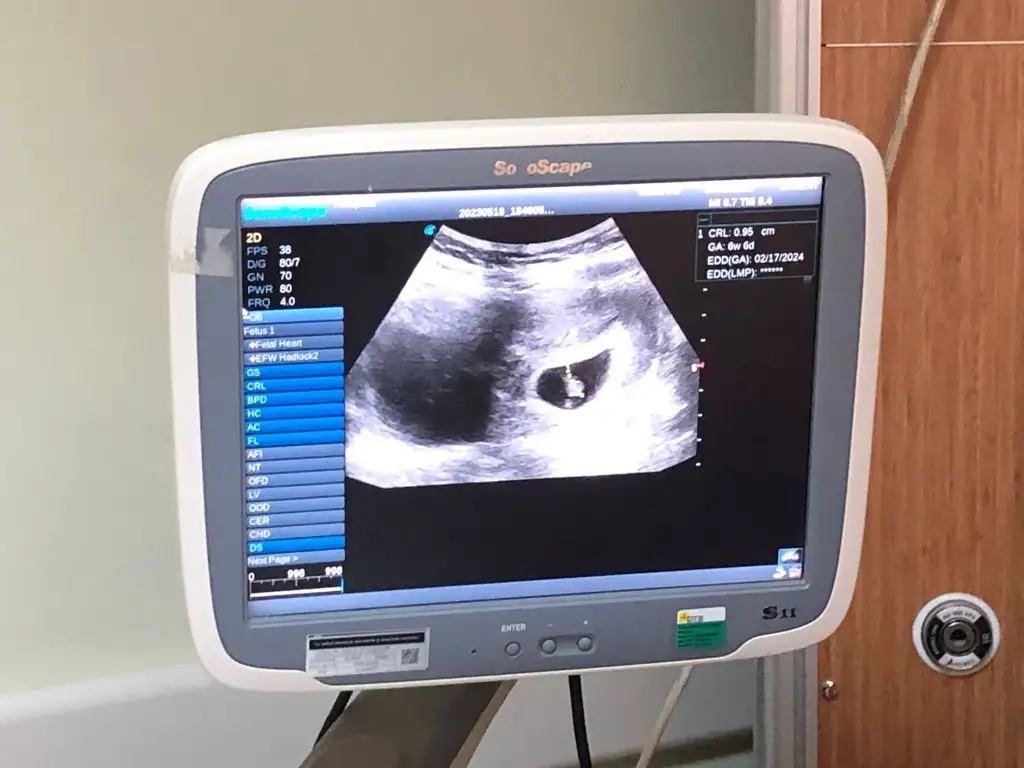

Ramiz teorisi kesede bebek sağ taraftaysa erkek sol taraftaysa kız ama karından bakılan ultrason resminde ayna gibi düşün canım sağ tarafta ise aslında sol oluyor kız solda ise sağ taraf oluyor erkekNasıl anlıyorsunuz anlamadım ben![]()

AnlamadimRamiz teorisi kesede bebek sağ taraftaysa erkek sol taraftaysa kız ama karından bakılan ultrason resminde ayna gibi düşün canım sağ tarafta ise aslında sol oluyor kız solda ise sağ taraf oluyor erkekbiraz karışık ama

Bebeğin yerleşim yerine göre teori

Şuna göre bakılıyor kız oluyor sanki seninki canım